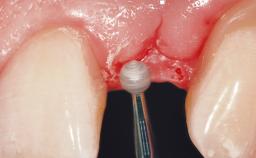

Late Flapless Placement of an Implant in a Maxillary Left Central Incisor Site